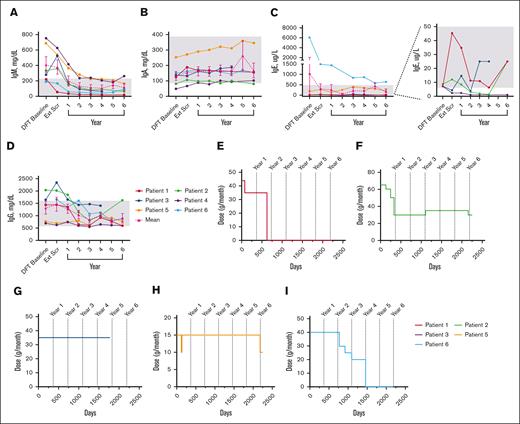

Mean IgM levels fell WNLs by year 1 (198.5 mg/dL); IgA (154.3 mg/dL), IgE (306.5 ug/L), and IgG (1469.0 mg/dL) levels fell WNLs by extension screening (Figure 5A-D). IgG subclass data beyond year 1 were only available for patients 5 and 6 (see supplemental Figure 3).

Changes in serum immunoglobulin levels and IRT throughout treatment with leniolisib. (A) Individual and mean IgM values over time. n values for part 1 baseline, Ext Scr, and years 1, 2, 3, 4, 5, and 6 are as follows: 6, 6, 6, 6, 6, 6, 3, and 5, respectively. (B) Individual and mean IgA values over time. n values for part 1 baseline, Ext Scr, and years 1, 2, 3, 4, 5, and 6 are as follows: 6, 6, 6, 6, 6, 6, 2, and 5, respectively. (C) Individual and mean IgE values over time. The graph on the far left illustrates all individual and mean IgE values over time. The far-right portion depicts individual IgE values for P1 through P4 over time as indicated by the dotted lines. n values for part 1 baseline, Ext Scr, and years 1, 2, 3, 4, 5, and 6 are as follows: 6, 6, 6, 5, 6, 6, 2, and 5, respectively. (D) Individual and mean IgG values over time. n values for part 1 baseline, Ext Scr, and years 1, 2, 3, 4, 5, and 6 are as follows: 5, 6, 6, 6, 6, 6, 3, and 5, respectively. For values that were <, the actual number was entered to graph data. IRT usage in (E) P1, (F) P2, (G) P3, (H) P5, and (I) P6 over time. Day 0 is the DFT baseline. Gray boxes in panels A-D indicate age-matched normal ranges from LabCorp.31-34 Error bars are ± standard error of the mean.

Changes in serum immunoglobulin levels and IRT throughout treatment with leniolisib. (A) Individual and mean IgM values over time. n values for part 1 baseline, Ext Scr, and years 1, 2, 3, 4, 5, and 6 are as follows: 6, 6, 6, 6, 6, 6, 3, and 5, respectively. (B) Individual and mean IgA values over time. n values for part 1 baseline, Ext Scr, and years 1, 2, 3, 4, 5, and 6 are as follows: 6, 6, 6, 6, 6, 6, 2, and 5, respectively. (C) Individual and mean IgE values over time. The graph on the far left illustrates all individual and mean IgE values over time. The far-right portion depicts individual IgE values for P1 through P4 over time as indicated by the dotted lines. n values for part 1 baseline, Ext Scr, and years 1, 2, 3, 4, 5, and 6 are as follows: 6, 6, 6, 5, 6, 6, 2, and 5, respectively. (D) Individual and mean IgG values over time. n values for part 1 baseline, Ext Scr, and years 1, 2, 3, 4, 5, and 6 are as follows: 5, 6, 6, 6, 6, 6, 3, and 5, respectively. For values that were <, the actual number was entered to graph data. IRT usage in (E) P1, (F) P2, (G) P3, (H) P5, and (I) P6 over time. Day 0 is the DFT baseline. Gray boxes in panels A-D indicate age-matched normal ranges from LabCorp.31-34 Error bars are ± standard error of the mean.

IRT use

Five patients received IRT at baseline; 2 patients discontinued and 2 reduced dose (Figure 5E-I). After IRT discontinuation, immunoglobulin levels remained WNLs through year 6 for both patients, excepting consistently high IgE in 1 patient. After IRT reduction in 1 patient, IgA was low whereas IgG was high at year 6, while another patient had low IgG3 at year 5. All 4 patients experienced a total of ≤4 infections each after termination or decrease in dosage.